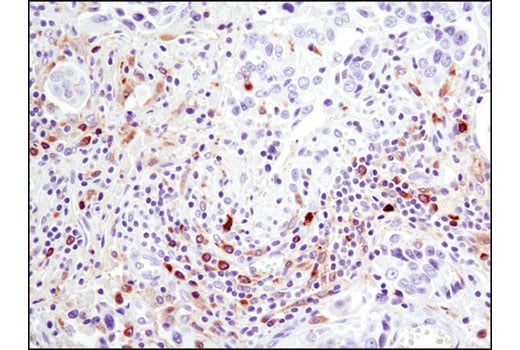

Immunohistochemical analysis of paraffin-embedded human squamous cell lung carcinoma using Btk (D3H5) Rabbit mAb performed on the Leica® Bond™ Rx.